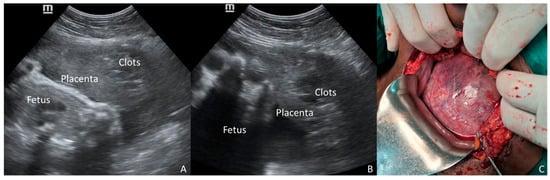

Figure 2.

A 32-year-old multigravid woman at 33 weeks of gestation, who was admitted for preeclampsia, experienced a sudden onset of severe hypertension associated with epigastric pain. POC-US was promptly performed along with lab investigation and stabilizing therapy. While the anterior placenta was normal, a dishomogeneous and hyper-hypoechoic mass was noticed between the placental tissue and the uterine wall (A,B). High suspicion of partial concealed abruption was raised. Emergency CS was performed without delay. The diagnosis of massive PA was confirmed at surgery, and a Couvelaire uterus was demonstrated (C). Lab tests concurrently confirmed HELLP syndrome. Placental abruption (PA) is a devastating obstetric emergency complicating approximately 1% of pregnancies and remains a leading cause of perinatal mortality and severe maternal morbidity [1,2]. Given that the diagnosis of PA is primarily clinical and traditional diagnostic tools like ultrasonography (US) and Doppler are notably limited in their predictive value [1,2], classifying the severity of PA has become critical. Two-thirds of PA cases are defined as severe, carrying a distinctively higher morbidity risk profile compared to mild abruption or non-abruption cases [3]. The diagnosis is complicated in cases of concealed placental abruption—where external hemorrhage is absent—or when the primary symptom is abdominal pain. These presentations are consistently associated with significantly poorer outcomes, including higher rates of intrauterine fetal death (IUFD) and severe maternal complications like disseminated intravascular coagulation (DIC) and uteroplacental apoplexy [4,5]. Indeed, in a significant minority of cases, neither vaginal bleeding nor pain is present, rendering the diagnosis dependent solely on non-specific systemic signs [6]. The presence of hypertensive disorders of pregnancy (HDP)—including severe preeclampsia, eclampsia, and Hemolysis-Elevated Liver enzymes-Low Platelets (HELLP) syndrome—acts as a significant, compounding risk factor for PA. The co-occurrence of PA and HDP is associated with poorer maternal and neonatal outcomes, including higher rates of severe abruption and stillbirth, compared to PA occurring in normotensive women [7,8,9]. Furthermore, in patients with preeclampsia, symptoms often shift away from typical vaginal bleeding toward non-specific central nervous system symptoms [10], masking the underlying abruption. Standard management for severe HDP dictates prompt delivery after maternal stabilization. The decision between induction of labor (IOL) versus immediate CS is critical. While IOL may be preferred, the presence of a massive, concealed PA makes CS mandatory to expedite delivery and prevent catastrophic hemorrhage. Traditional US has notoriously low sensitivity for diagnosing PA, with retroplacental hematoma seen in only a minority of cases (as low as 15%) [6]. However, given the extreme risk associated with occult PA in the setting of severe HDP, any suspicious finding demands attention. Point-of-Care Ultrasound (POC-US), a valuable tool for rapid, bedside evaluation of critically ill patients [11,12], offers a unique opportunity for quick, targeted diagnostic imaging to assess the placental interface. We presented two illustrative cases of severe HDP—one with eclampsia and one with HELLP syndrome—managed at St. Luke Catholic Hospital in Wolisso, Ethiopia. In both instances, POC-US revealed a retroplacental mass, which raised the suspicion of concealed PA and influenced the decision-making process toward immediate surgical delivery. These cases underscore the potential of POC-US findings to act as a contributing triage tool for obstetric emergencies occurring in a low-resourced setting. The two clinical cases presented here vividly illustrate the critical diagnostic and therapeutic challenges posed by concealed PA when complicating severe HDP. In both patients, the suspicion of PA was raised by a retroplacental mass visualized via POC-US, leading to the choice of immediate CS. Crucially, both patients lacked the classic symptoms of PA (vaginal bleeding or severe abdominal pain), placing them into the high-risk “concealed” category. Although several conditions may increase the risk of PA—i.e., advanced maternal age, trauma, amniotic fluid abnormalities, cocaine use—the literature consistently highlights the severe synergistic effect of HDP, compounded by the concealed presentation [1,7,9]. Studies focusing on symptom types demonstrate that when PA is concealed or presents primarily with abdominal pain, maternal and neonatal outcomes are dramatically poorer compared to revealed cases (vaginal bleeding) [4,5]. Although POC-US cannot be promoted as a primary screening tool for placental abruption due to its limited sensitivity, we emphasize its role as a multipurpose triage tool. The 2026 ISUOG Practice Guidelines (Recommendation 2) suggest POC-US for placental localization in cases of antepartum hemorrhage [12]. However, as demonstrated in our cases, POC-US performed for standard indications—such as assessing fetal viability or gestational age—can incidentally reveal retroplacental masses even in the absence of overt bleeding. It is well-established that ultrasonography (US) is neither sensitive nor specific for the diagnosis of PA, with detection rates ranging from 25% to 60% [13]. The lack of robust specificity data means that a positive US result does not definitively confirm PA. However, in the critical context of severe HDP combined with the high fatality rates of concealed PA, the objective evidence of a retroplacental mass, even if only raising suspicion, may dramatically shift the risk–benefit analysis toward immediate surgical delivery to prioritize maternal and perinatal safety. Our first case demonstrates the risk of delayed intervention; despite the POC-US finding of a retroplacental mass, a surgical delay resulted in intrauterine fetal demise (IUFD) and severe maternal morbidity, namely obstetric hemorrhage. This tragic outcome suggests considering a positive POC-US finding in this high-risk scenario as an indicator of surgical emergency. In contrast, the second case highlights the optimizing role of POC-US; the finding of the placental mass provided objective evidence to bypass potential induction and proceed directly to immediate CS, contributing to a favorable maternal and neonatal outcome despite the massive PA found intraoperatively. In both cases, the US examination was performed by Integrated Emergency Surgical Officers, who are non-medical providers trained according to a specific national program that ensures competence in obstetric POC-US. The utility of this technology is amplified in low-resource settings, where access to specialized diagnostic services or continuous cardiotocographic monitoring (CTG) is typically limited [11,12,14,15]. A rapid, bedside POC-US scan, confirmed to be reliable in similar environments, becomes a life-saving triage tool [11,12,14,15]. It may support the clinical team to differentiate a severe HDP requiring medical stabilization and labor induction from one complicated by an acute, catastrophic event—concealed PA—that requires immediate operative delivery. The objective visualization of suggested findings provides their necessary confirmation in an environment where clinical judgment must be promptly offered but is often based on minimal resources. Nonetheless, the technical limitations of POC-US must be recognized; it remains highly operator-dependent and carries a risk of false-negative results, particularly in cases of posterior placentation where fetal shadowing may obscure the retroplacental interface. In conclusion, this report demonstrates that a positive POC-US finding consistent with retroplacental hemorrhage in the setting of severe HDP—eclampsia or HELLP syndrome—should be viewed as a critically significant indicator of concealed PA, suggesting a shift toward immediate CS. The reliability of POC-US devices in low-resource settings, combined with their speed and accessibility, makes them a powerful tool for optimizing emergency obstetric management. Additional prospective research is warranted to accurately determine the positive and negative predictive value of POC-US in the high-risk obstetric population.